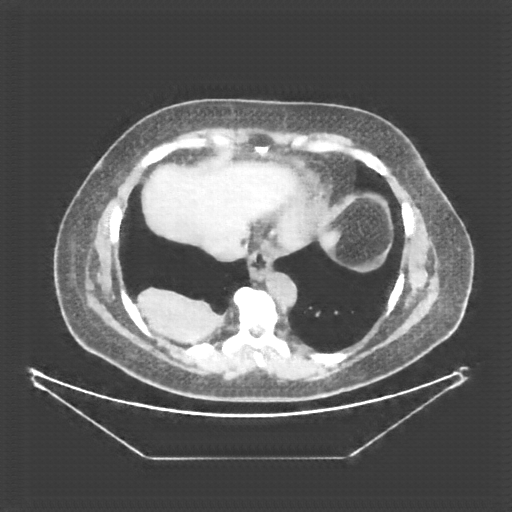

Image Grid

4×3 grid: Rows show different image types (Original NATIVE, Reconstructed NATIVE, Original VENOUS, Generated VENOUS), Columns show windowing techniques (No Window, Lung Window, Mediastinum Window)

Reconstructed NATIVE CT scan (cycle consistency)

No window - Raw intensity values

Generated VENOUS CT scan (A→B translation)

No window - Raw intensity values

Generated VENOUS CT scan (A→B translation)

Lung window (WL -600, WW 1500 → Low −1350, High +150)